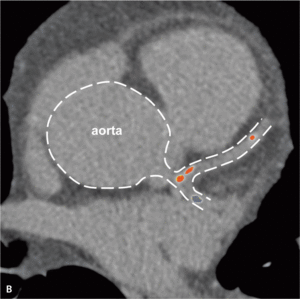

Rycina 4. Progresja zmian miażdżycowych w tętnicach wieńcowych u bezobjawowego chorego z toczniem rumieniowatym układowym w rocznej obserwacji.

Badania obrazowe dowiodły, że mimo stabilnego okresu choroby oraz małej podtrzymującej dawki kortykosteroidów u młodych chorych z SLE miażdżyca tętnic wieńcowych postępuje szybko [33]. Rycina 4 przedstawia progresję zmian miażdżycowych uwidocznioną metodą wielorzędowej tomografii komputerowej, do której doszło u bezobjawowego chorego z SLE w rocznej obserwacji. Duże ryzyko objawowej postaci choroby niedokrwiennej serca obserwowane już u młodych chorych z SLE pozwala przypuszczać, że obecność klasycznych czynników ryzyka miażdżycy nie stanowi w tej grupie głównego mechanizmu patogenetycznego. Zgodnie z oczekiwaniami wykazano brak istotnego wpływu otyłości, nadciśnienia tętniczego, palenia tytoniu, hiperlipidemii lub cukrzycy na obecność i nasilenie zwapnień w tętnicach wieńcowych oraz zaburzeń perfuzji mięśnia serca [24]. Uogólniony proces zapalny, manifestujący się podwyższeniem stężenia białka CRP oraz obniżeniem stężenia składowych C3c i C4 układu dopełniacza, nie wpływa istotnie na rozwój zmian miażdżycowych w młodym wieku [24], chyba że stężenie CRP jest przewlekle istotnie podwyższone i przekracza 20 mg/l [34].